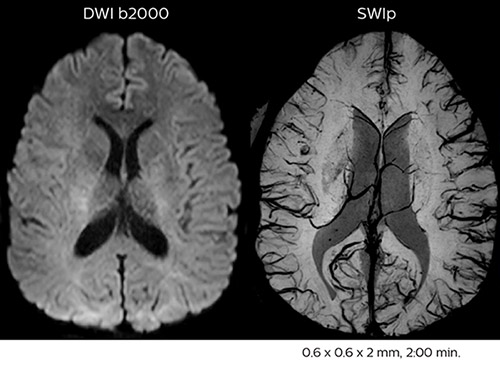

In this patient with acute right motor deficit and aphasia, the b2000 diffusion weighted image is normal. The SWIp image demonstrates more prominent veins in the right hemisphere, which could reflect increased deoxyhemoglobin contents. Fast ASL shows low CBF regions in the left frontal lobe. A follow-up ASL after one hour demonstrates high CBF values in the same area. The final diagnosis was migraine with aura.